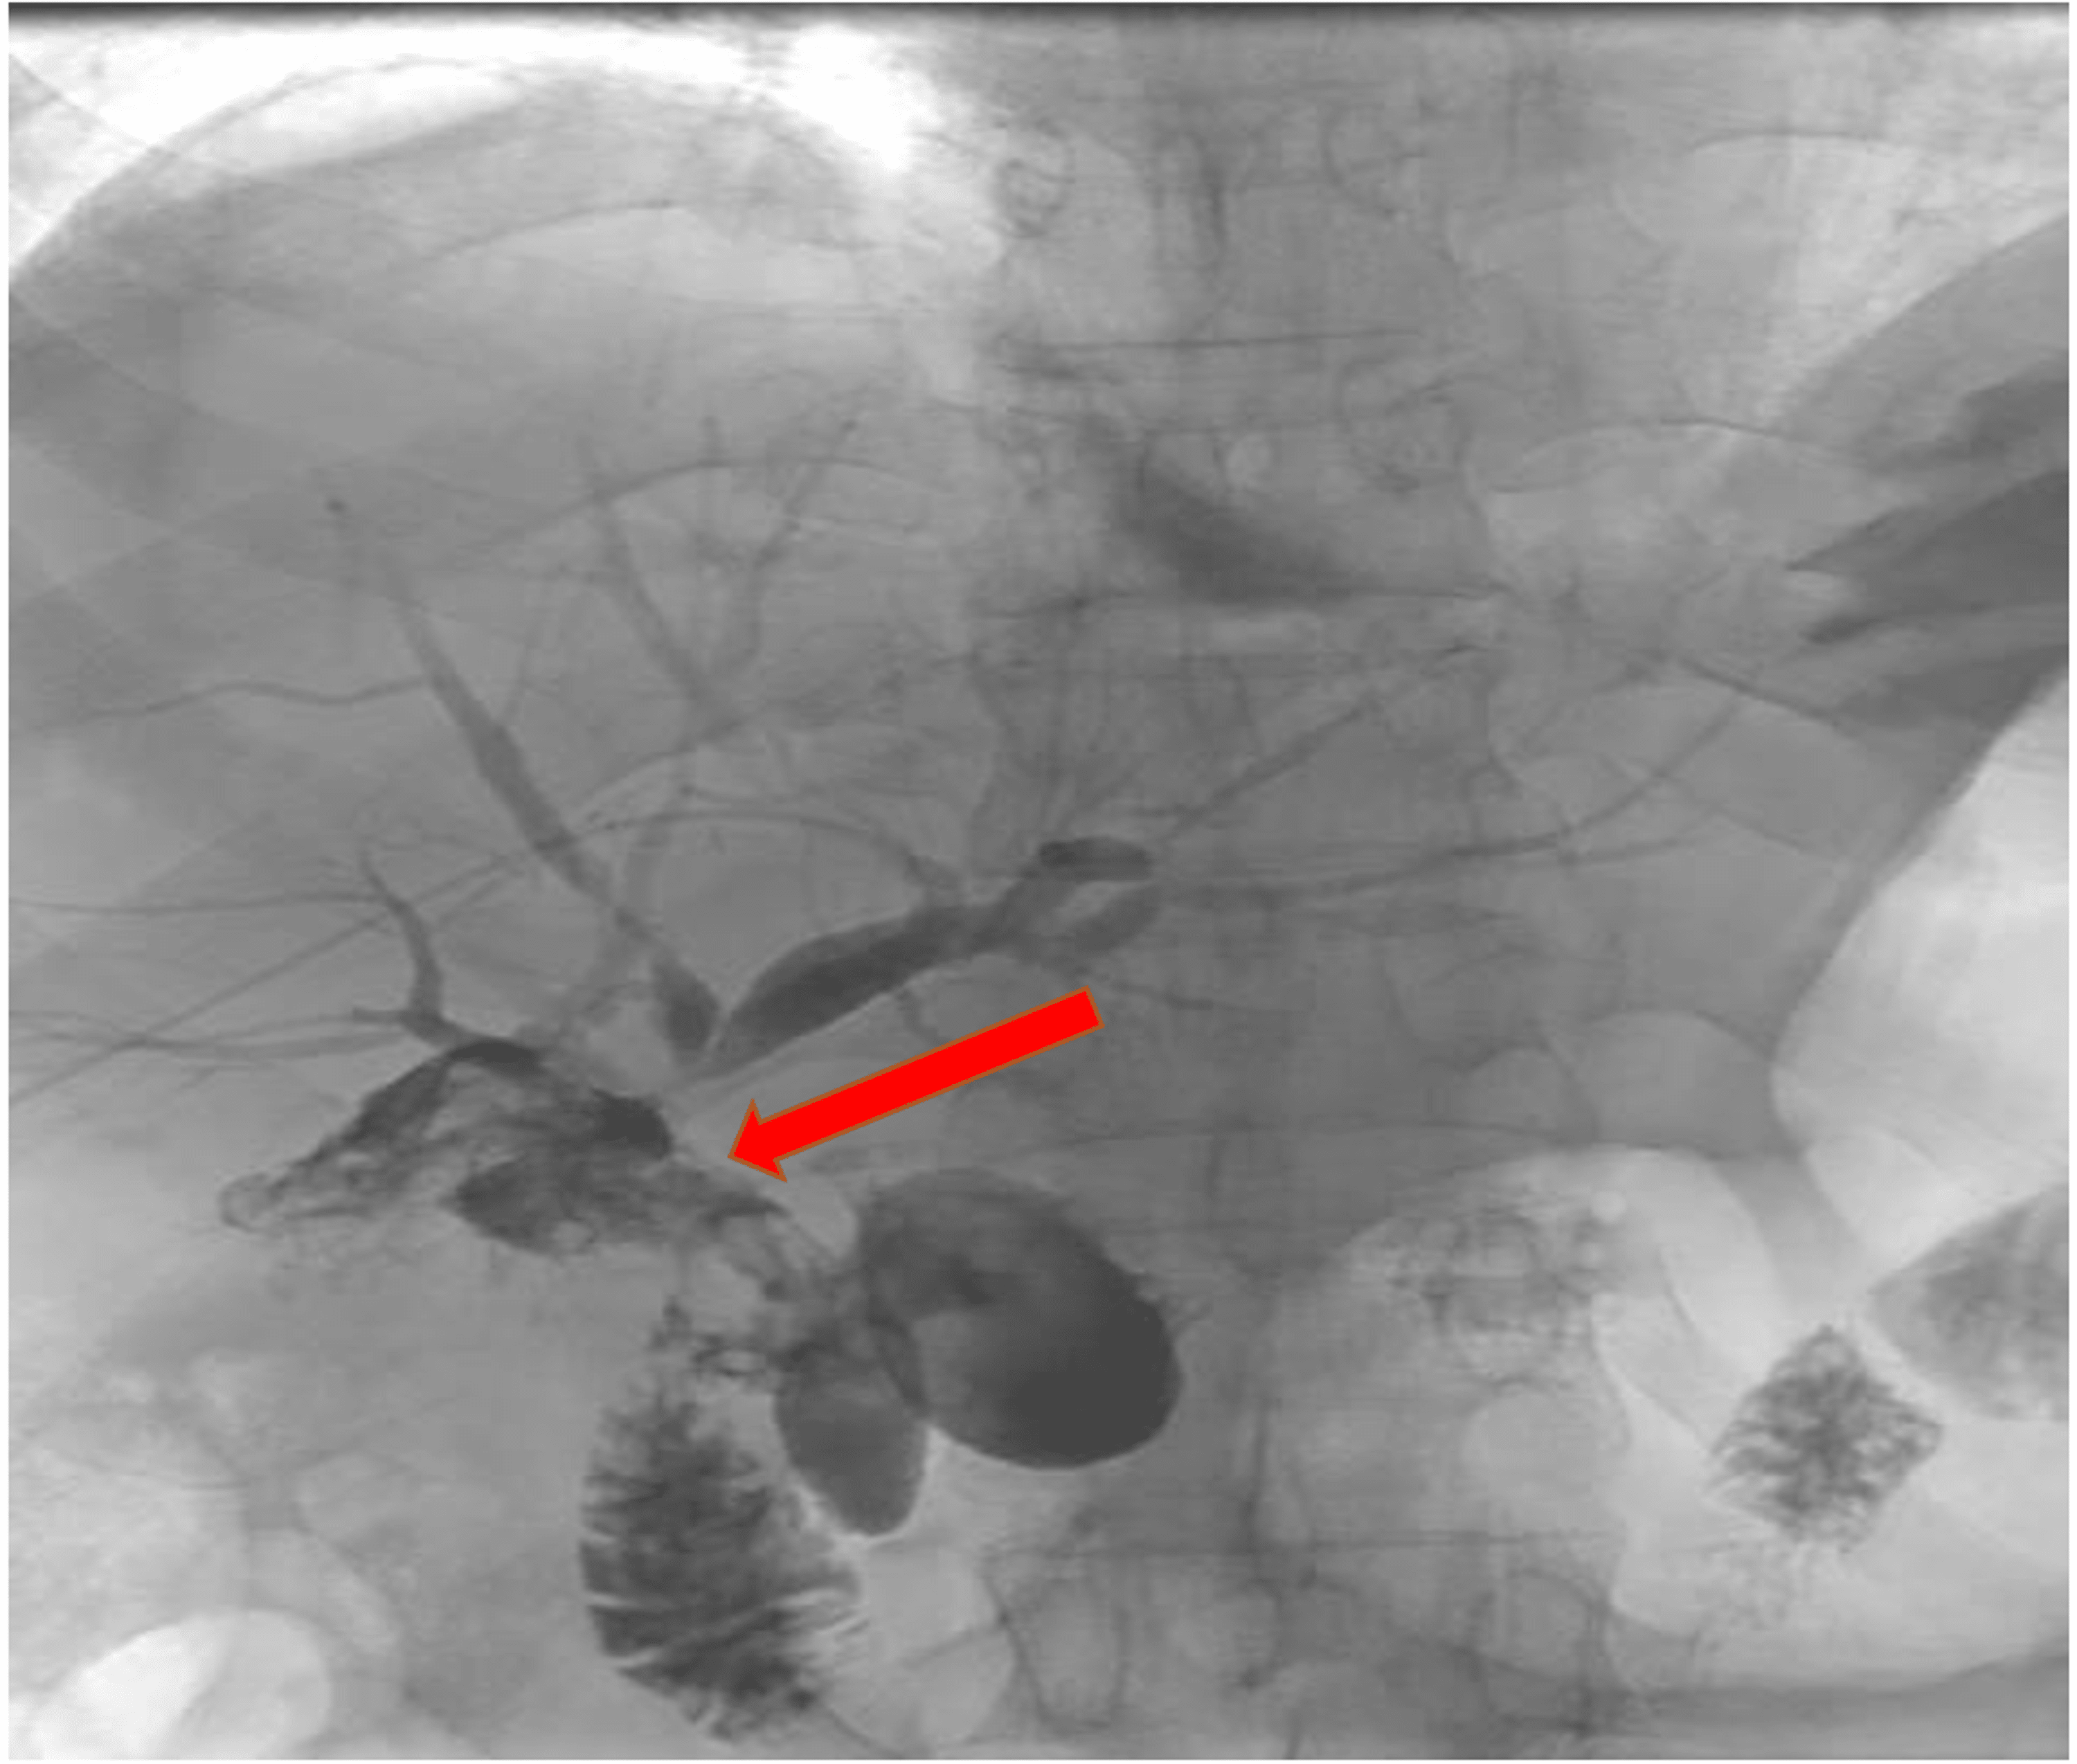

Cureus Percutaneous Management of Hepatic Duct Injury Using Extra Hepatic Flexure Pain Right Side vitals should be normal in a person with splenic flexure syndrome, other than their heart rate perhaps being elevated due to acute pain. The right colic flexure is also. A large bowel stricture with shouldering at the hepatic flexure consistent with colonic carcinoma. It can weigh up to 4 pounds (1.8 kilograms). In the anatomy of the human digestive. Hepatic Flexure Pain Right Side.

GI Bleed in Hepatic Flexure Colon Case Studies CTisus CT Scanning Hepatic Flexure Pain Right Side splenic flexure syndrome is a condition that causes gas to become trapped inside flexures — or curves — within your. Mendelson, md september 21, 2024. The right colic flexure is also. vitals should be normal in a person with splenic flexure syndrome, other than their heart rate perhaps being elevated due to acute pain. the liver is. Hepatic Flexure Pain Right Side.

GI Bleed in Hepatic Flexure Colon Case Studies CTisus CT Scanning Hepatic Flexure Pain Right Side splenic flexure syndrome is a condition that causes gas to become trapped inside flexures — or curves — within your. vitals should be normal in a person with splenic flexure syndrome, other than their heart rate perhaps being elevated due to acute pain. In the anatomy of the human digestive tract, there are two colic flexures, or curvatures. Hepatic Flexure Pain Right Side.